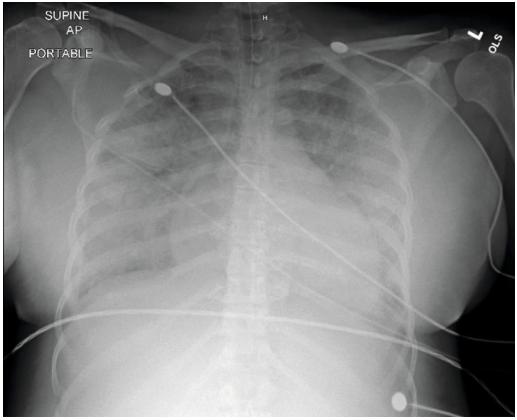

在住院第二天,患者接受了第二剂倍他米松,并注意到当天下午血压再次升高至170-180/90-100 mmHg。因此,决定进行紧急剖宫产。剖腹产分娩一名体重1195 g的女婴,估计失血量为590 mL,术后血红蛋白从11.8 mg/dL降至9.7 mg/dL。患者随后接受了30 U的连续催产素和1000 mL生理盐水输注,作为子宫和产后硫酸镁预防癫痫发作。患者的净摄入量和净输出量记录为+5981 mL。在22:40,患者开始主诉在使用4 L鼻插管时呼吸困难,但保持了94%-100%的充足氧饱和度。硫酸镁已停用。23:00时,血氧饱和度迅速降到82-87%,肺部听诊双侧出现爆破音。血氧饱和度继续下降到60-70%,患者变得没有反应。成功插管6分钟后患者恢复自主循环,随后被转移到密歇根州立大学接受进一步的护理和监测。A/P胸片显示轻度心脏肿大伴中度肺水肿(图1)。然后用三剂20毫克速尿进行利尿。

图1. 胸部X光片显示心肺骤停后轻度心脏肿大伴中度肺水肿。